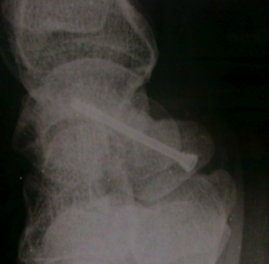

Le traitement des fractures déplacées est chirurgical. Il consiste à réduire le déplacement puis à stabiliser la fracture (par vis ou broches).

La majorité des fractures opérées consolident.